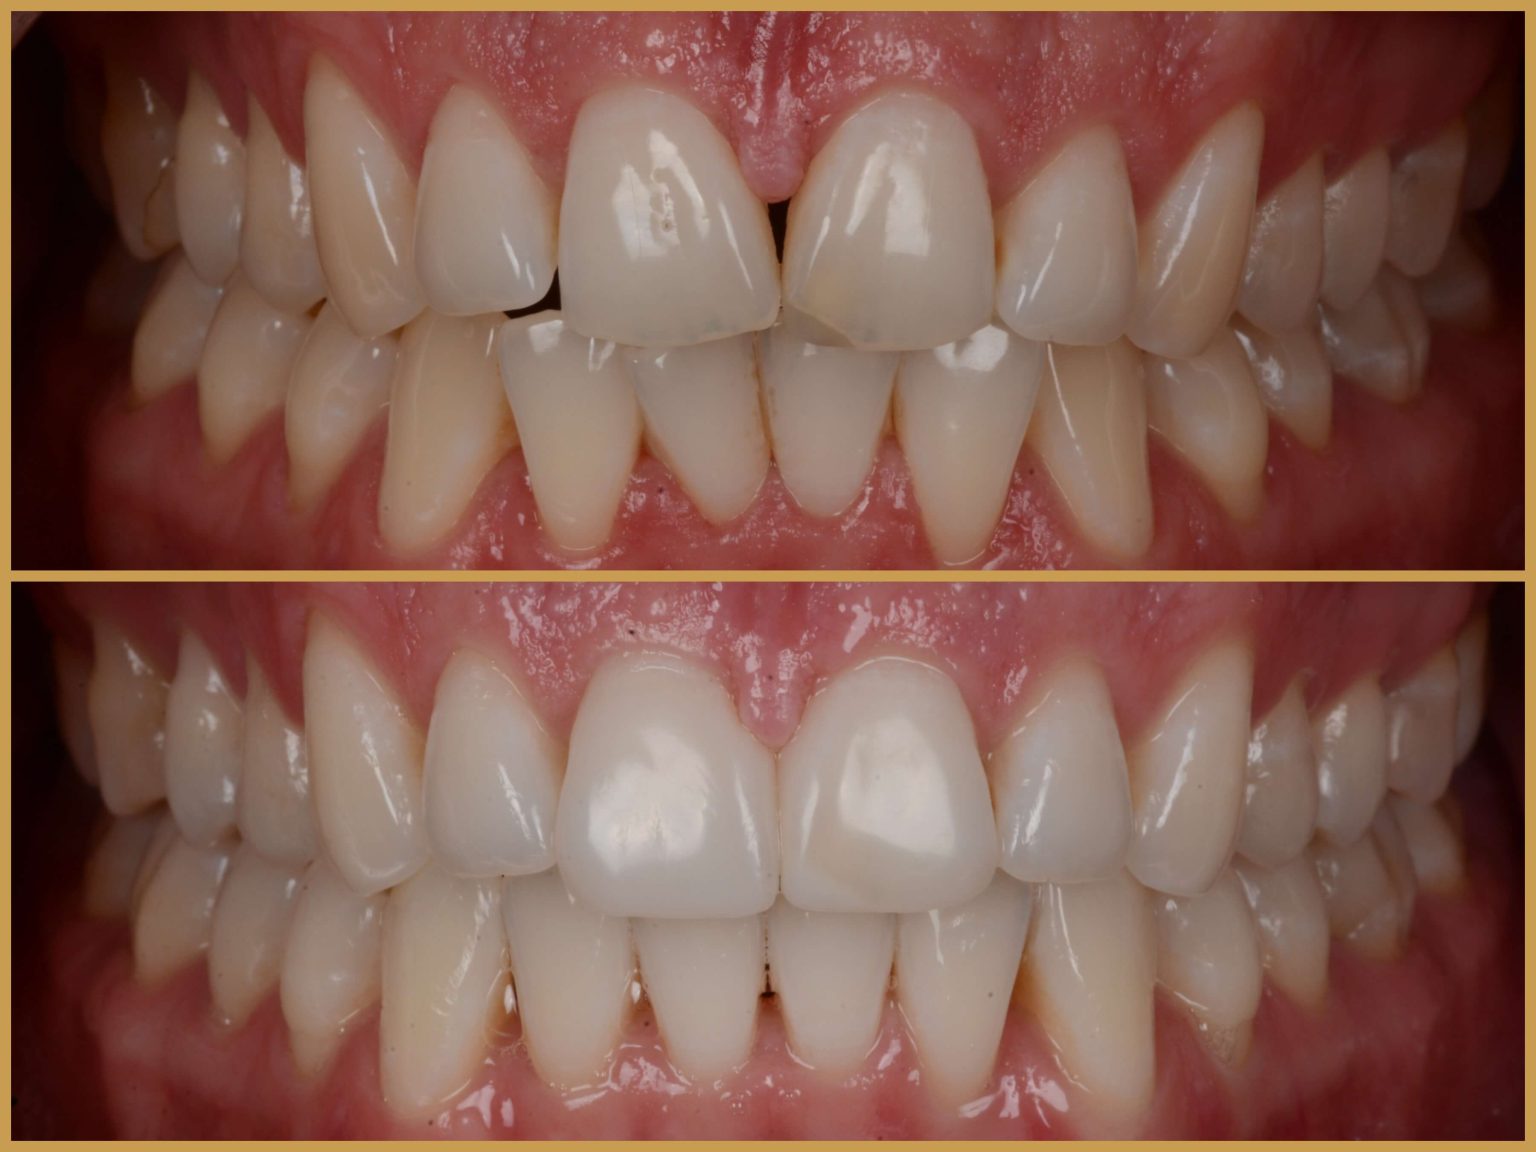

Amennyiben csak részlegesen hiányoznak fogak és azokat fogimplantátumokkal helyettesítettük, akkor rövidebb hidak készülnek, lehetőség szerint szintén csavarrögzítéssel. Előfordul, hogy csupán egyetlen fog hiányzik és annak helyére kerül beültetésre fogimplantátum. Ha ez a hiányzó fog a mosolyzónában helyezkedik el, akkor kiemelt és kritikus fontosságú a fogimplantátumra készülő fogpótlás természetes megjelenése.

Ez a feladat speciális felkészültséget igényel orvosi és fogtechnikusi oldalról egyaránt. Ilyenkor különös tekintettel kell lenni a fogíny lefutására és annak a természetes szomszédos fogakhoz való kialakítására. Bodrogi doktor nemzetközi előadásainak fő témája az esztétikai zóna ellátása különböző fogimplantációs megoldásokkal. Azonban az esztétika mellett a fogsorzáródás (harapás) optimalizálásán keresztül a helyes funkció kialakítása is kiemelt fontosságú a fogimplantációs beavatkozások kapcsán.